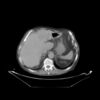

| (b) Portal venous phase (template dataset, ) | (c) Registered template, (CR-based method) | (d) Registered template, (proposed method) | |

| Figure a: Arterial phase (reference dataset, ) | |||

For the assessment of the proposed method, we carry out a comparison with the purely intensity-based variational method recently presented by the authors of this work in [26]. This CR-based approach was reported to outperform publicly available state-of-the art methods such as Elastix and ANTs in the medical setting. As can be seen in Fig.1, the proposed framework shows excellent results for the three considered registration scenarios (arterial-portal, arterial-non-contrast and portal-non-contrast), reaching average values of 1.47, 1.44 and 1.52 bits in terms of mutual information, corresponding to the arterial-portal, arterial-non-contrast and portal-non-contrast cases, respectively; this represents a mean improvement of 28.9%, 48.45% and 51.16% in relative terms of mutual information, thus outperforming the CR-based registration algorithm, which achieves a mean improvement of 26.48%, 44.22% and 43.25%, respectively. Additionally, due to the analogous behavior (i.e., comparable final values of mutual information) of the proposed method in the three scenarios, all available experiments can be grouped into one ensemble in order to assess a more comprehensive validation of the actual registration error. A ground truth was established by an expert in the form of identifiable anatomical locations (landmarks) for all experiments. The registration errors were then obtained by computing the spatial distance between the corresponding landmarks in the reference and registered template datasets. Figures Fig.2(a) and Fig.2(b) show through box plots the registration error (in millimeters) achieved by the methods under comparison, gathering the results from the three considered registration scenarios. These box plots collect the final spatial distances between corresponding landmarks, along with the median distance error and its statistical significance (notch showing the 95% confidence interval of the true median). According to Fig.2(b), the proposed method significantly improves on the registration error of the CR-based approach, since it reduces the initial median error from 9.50 mm to a residual median distance between landmarks of 1.41 mm, decreasing at the same time the outliers occurrence.

In addition to the previous measurements, the visual outcomes of two of the experiments are shown in figures Fig.3 and Fig.4, whose purpose is to highlight the most illustrative differences (from a medical point of view) between the results provided by the compared methods. In Fig.3, we observe a normal size of the liver, with discretely irregular contours and homogeneous signal intensity. In hepatic segment II, there is a lesion of 40 mm of maximum axis, encapsulated and with well-defined contours and heterogeneous enhancement in arterial phase (after administration of intravenous contrast), suggestive of hepatocellular carcinoma (HCC). In this slice of the CT scan, we can also observe the aorta that shines in the arterial phase, the lower area of the stomach and the upper area of the spleen. In Fig.4, the liver has a normal size with discretely irregular contours in relation to changes due to chronic liver disease. In hepatic segment IV, a 36 mm diameter focal lesion is identified, which has arterial phase enhancement with a small area of necrosis of 13 mm; it corresponds to a HCC previously chemoembolized with partial necrosis. In this slice of CT, we can also observe the aorta, the gastric chamber and the spleen. When comparing the two methods under study, it can be seen how in Fig.3 the resulting registered datasets are very similar. However, looking closely, it can be noticed that in the right part of the image (left side of the patient) the shape and width of the structures corresponding to the stomach and the spleen in Fig.3(d) match better those in the reference dataset. Likewise, the part of the rib at the upper right of the image is more similar to the same region in the reference dataset by using the proposed method. Regarding the experiment shown in Fig.4, it can be easily appreciated how the geometrical matching (with respect to the reference dataset, Fig.4(a)) of the structures in the right side of the image (specially the gastric chamber) is visually more satisfactory in Fig.4(d). Moreover, the area of tumor necrosis which results from the proposed method is also slightly better aligned.